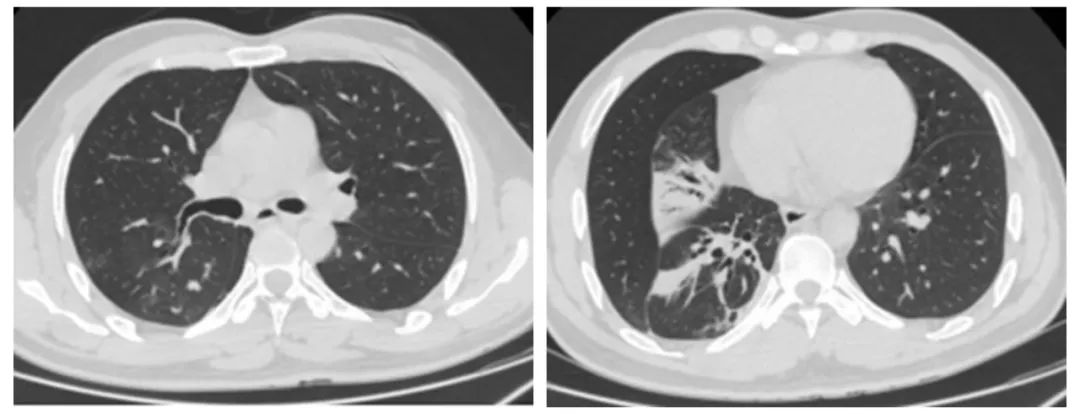

患者高某,男,45岁,因“咳嗽、咳痰5月”入院。胸部增强CT提示:1、右主支气管下段、右中间支气管占位性病变,并右肺下叶不张;2、双肺上叶、左肺下叶多发结节灶。影像学检查提示恶性肿瘤导致的阻塞性肺不张,但初步的病理活检并不支持,经气管镜组织活检提示:(右主支气管)黏膜慢性溃疡并肉芽肿形成。罗少华主任查房指出,患者为中青年男性,无吸烟史,右主支气管至右中间支气管占位,并右下叶肺不张,气管镜下活检病理未见肿瘤改变,可能跟取材表浅有关,但不完全排除非肿瘤性病变,建议行硬质支气管镜下支气管肿物钳除+激光消融术,取较大块组织行病理检查以明确诊断,同时,解除其气道梗阻。

术后复查胸部CT示:右主支气管新生物清除,右下肺下叶较前明显复张